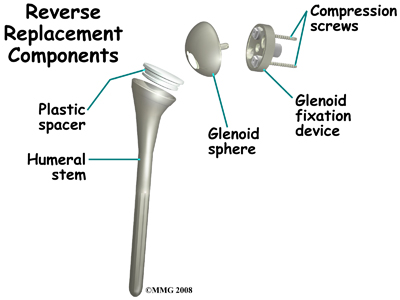

The reverse shoulder prosthesis (artificial joint) is made up of two parts. The humeral component replaces the humeral head, or the ball of the joint. The glenoid component replaces the socket of the shoulder, which is actually part of the scapula.

The reverse shoulder prosthesis (artificial joint) is made up of two parts. The humeral component replaces the humeral head, or the ball of the joint. The glenoid component replaces the socket of the shoulder, which is actually part of the scapula.

In the traditional artificial shoulder prosthesis, the glenoid prosthesis is a shallow socket made of plastic and the humeral component is a metal stem attached to a metal ball that nearly matches the anatomy of the normal shoulder. In the reverse shoulder replacement, the ball and the socket are reversed such that the ball sticks out of the shoulder itself.

The humeral component is a combination of a metal stem that fits into the marrow cavity of the upper humerus and, on top of the metal stem, a plastic socket. This plastic socket fits onto the humeral component to create a ball and socket type bearing. The glenoid component is usually made of two parts: a metal tray and a metal ball. The metal tray (base plate) attaches directly to the bone. This base plate is inserted into a small peg hole drilled into the bone and is secured with special screws through the base plate into the bone. Attached to that metal tray, there is a metal ball that will fit into the plastic socket attached to the humeral component. The plastic is very tough and very slick, much like the articular cartilage it is replacing. This plastic is so tough that you could actually ice skate on a sheet of this plastic without causing it much damage.